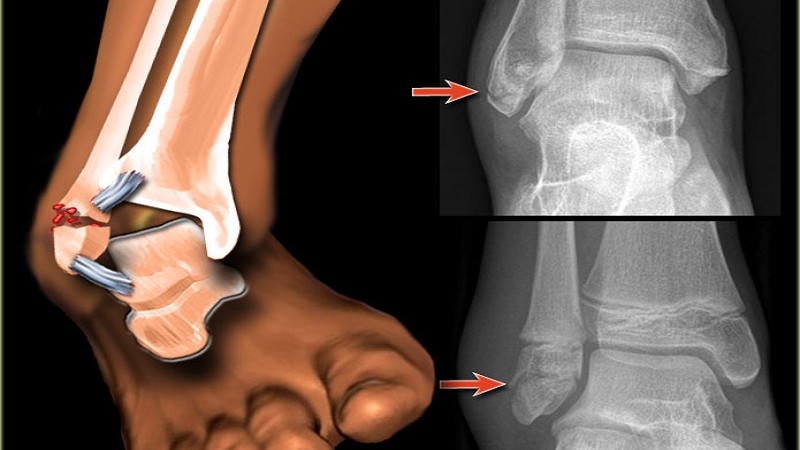

Переломы лодыжек встречаются у людей любого возраста и пола. Как правило, они возникают в результате нарушения координации движений и ухудшения физической формы человека. Трехлодыжечный перелом (Код по МКБ-10 – S82.8) характеризуется одновременным нарушением целостности медиальной и латеральной лодыжки, а также повреждением большеберцовой кости. Очень часто, подобная травма сопровождается осложнениями: смещением костных фрагментов, нарушением целостности кровеносных сосудов и нервных волокон.

В результате подобных движений возникает перелом двух лодыжек и передней, либо задней части большеберцовой кости. При этом, у пострадавшего отмечаются следующие клинические признаки: